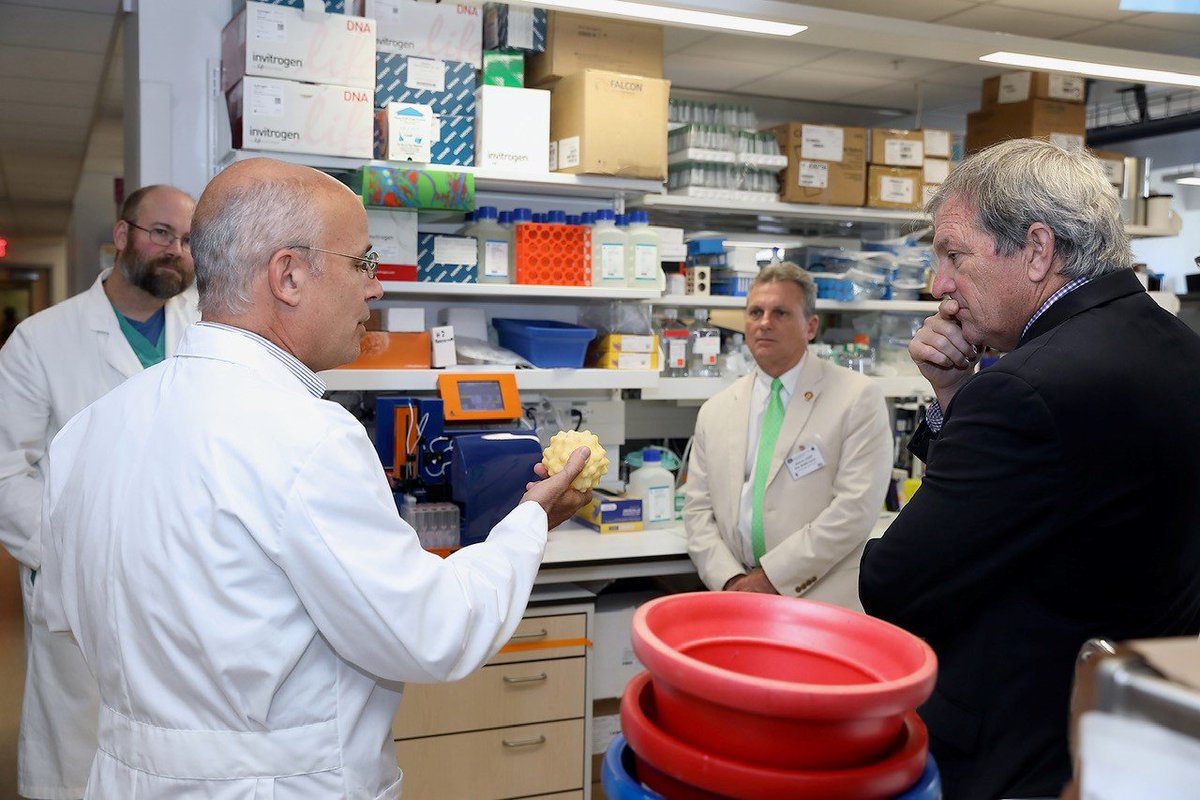

Congressional Cancer Survivors Caucus Visits NIH, NIDCR

During a July visit, members of the bipartisan Congressional Cancer Survivors Caucus learned about NIH’s cancer-related research. Among their tour stops was the lab of NIDCR intramural scientist John Chiorini, PhD, who discussed his gene therapy clinical trials for patients with cancer therapy-induced dry mouth. Later, NIDCR Clinical Director Janice Lee spoke with the visitors about the link between oral and overall health.